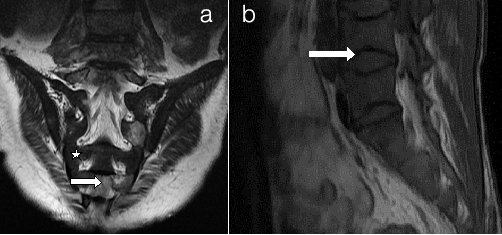

Persistent red marrow a) Sacrum b) Spine (a) Coronal T2WI of sacrum and (b) Sagittal T1WI of Spine shows low signal intensity marrow (white star) compared to adjacent muscles suggestive of cellular (red) marrow. There are multiple bony infarcts in S2, S4 and S5 vertebrae (small arrow). There are vertebral end plate concavities at multiple levels due to end plate infarction giving fish mouth appearance

Extramedullary haematopoiesis (a) T1Weighted Image (b) T2Weighted Image (a) Coronal and; (b) Axial MRI Images of Thoracolumbar spine. Extramedullary Haematopoiesis is seen as lobulated paravertebral soft tissue masses (arrow in b) with intermediate signal intensity on T1 and T2 weighted images similar to signal intensity of normal intrameduallary haematopoietic tissue. Also there is Persistent red marrow in vertebral bodies (double head arrow in a)